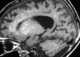

Cockayne syndrome (CS), also called Neill-Dingwall syndrome, is a rare and fatal autosomal recessive neurodegenerative disorder characterized by growth failure, impaired development of the nervous system, abnormal sensitivity to sunlight (photosensitivity), eye disorders and premature aging. Failure to thrive and neurological disorders are criteria for diagnosis, while photosensitivity, hearing loss, eye abnormalities, and cavities are other very common features. [Source: Wikipedia ]

Intracranial calcification

Leukodystrophy / leukoencephalopathy

Multiple intracranial calcification